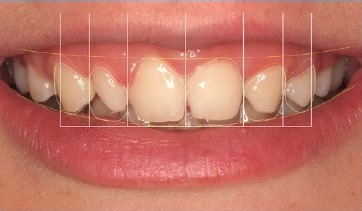

A 15-year-old patient presented with unilateral MLIA and microdontia (Figure 9). The left maxillary canine erupted mesially from its normal position, while the right maxillary lateral incisor was conical. Both central incisors were tipped to the left and associated with occlusal plane canting to the left. There was also an evident Bolton’s anterior discrepancy of 74.1 % (13, 12, 11, 21, 23, 24 / 43,42, 81, 71, 32, 33) due to maxillary asymmetric agenesis, a canine in place of the lateral incisor, and a conical contralateral (Figure 10). And due to agenesis of the mandibular central incisors and the presence of correspondent deciduous teeth. After the orthodontic treatment (Figure 11), the complexity of the asymmetric case required digital smile planning (Figure 12) and a diagnosis wax-up (Figure 13) to plan and visually demonstrate the desired result to the patient.

Left maxillary canine contouring procedures (Figures 8 and 9) were performed as indicated by the diagnostic wax-up.19 First, the canine eminence was reduced on the labial surface, and the tip of the canine was flattened to produce an incisal edge. Second, the distal incisal angle was slightly rounded to reproduce a lateral incisor. Third, ORMOCER® (ORganically-MOdified-CERamic) composite (Admira Fusion, VOCO, Cuxhaven, Germany) without bisphenol A (BPA) was added to the adjacent teeth to improve the distal and mesial dimensions of the left maxillary central incisor and left maxillary first premolar, thereby diminishing the canine and harmonizing the smile line (Figure 14). In addition, because the mandibular primary left central incisor presented mobility due to root resorption, it was extracted, and the mandibular primary right central incisor was restored (Figure 15).

A 19-year-old female patient presented with primarily esthetic concerns. An intraoral examination revealed a Class I right molar, a Class II left molar, and a deep bite (Figure 17). Orthodontic treatment was performed to obtain bilateral Class I molar and canine relationship and, in turn, improve the overbite and remove the traumatic occlusion responsible for the gingival recession on the left mandibular incisor. Bolton’s anterior analysis confirmed a dental discrepancy in the anterior sector to mandibular excess with a proportion of 83.1% (13, 12, 11, 21, 22, 23 / 43, 42, 41, 31, 32, 33). It was caused by the maxillary dental microdontia and the need to carry out esthetic restorations in the upper arch. A space was created on the distal surface of both microdontic lateral incisors to establish the Bolton’s proportion17 (Figure 18). After orthodontic treatment, shade selection was accomplished using a Vita Shade Guide (Figure 19), and dental bleaching was performed to optimize the harmony of the smile.